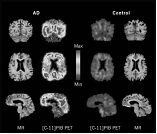

匹兹堡化合物B(PiB)在人类大脑的正电子发射断层扫描图像(PET)中照亮了淀粉样斑块

成像技术有助于鉴定大脑中与认知能力下降有关的变化。对进行期阿尔茨海默氏症患者施行MRI扫描,可揭示其颞叶和海马区缩小以及脑室扩大。海马是大脑中用于储存记忆和空间导航的区域,脑室是大脑容纳CSF的腔。FDG-PET研究显示,认知能力下降与大脑新陈代谢活动降低最密切相关。

ADNI开始不久,宾夕法尼亚州匹兹堡大学的研究人员开发出一种新颖的PET技术――他们使用一种称做匹兹堡化合物B(PiB)的放射性标记物,检测患者大脑中的淀粉样蛋白斑块。将这一技术结合CSF的测试,参与ADNI的研究人员现在能够确认随着大脑中聚合的β-淀粉样蛋白水平增加、CSF中可溶性β-淀粉样蛋白的减少。这不仅把PiB-PET确定为一种检测生物标记物的技术,还进一步确定了CSF中β-淀粉样蛋白的测量值可作为大脑病理学的可靠标记物。

通过匹兹堡化合物B(PiB)放射性标记物,以检测患者大脑中淀粉样蛋白斑块